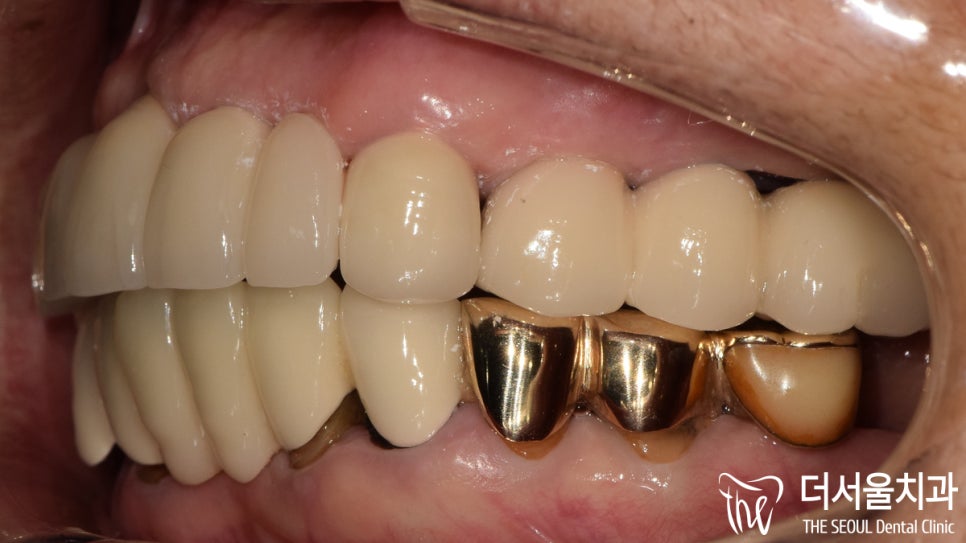

측면에서 관찰해 보니

치경부가 겉으로 드러난 것은 물론이며

다량의 치석들이 주변에 자리를 잡고 있었습니다.

통증이 느껴졌던 오래된 브릿지가

튼튼하고 심미성이 좋은 지르코니아로

바뀌어 있는 모습을 확인할 수 있습니다.

교합도 잘 맞물리고 있었으며

크라운도 인접치 형태에 맞춰

조화롭게 제작이 되었습니다.